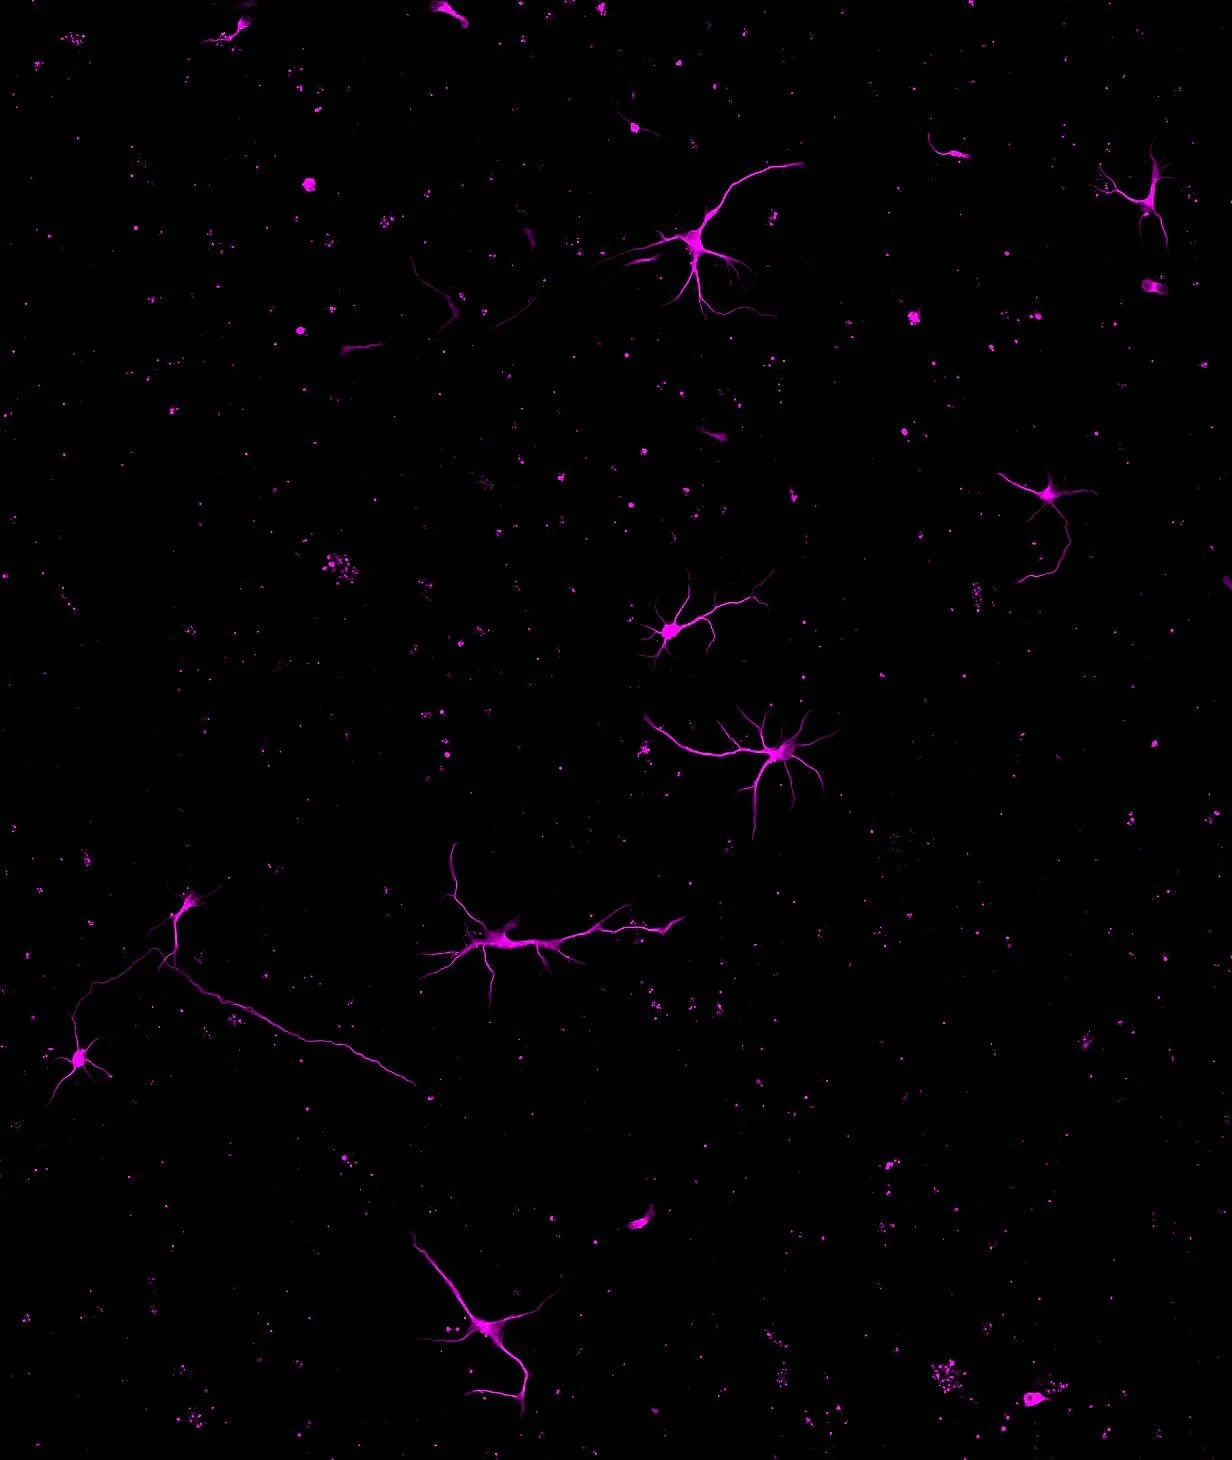

Brain-derived neurotrophic factor (BDNF) is a key neurotrophin that supports neuronal survival, differentiation, and synaptic plasticity. It plays a central role in learning, memory, and overall brain function. Alterations in BDNF signaling have been consistently observed across a wide range of diseases, including neurodegenerative disorders, psychiatric illnesses, and neurodevelopmental diseases. Disruptions in its pathways are considered fundamental contributors to disease mechanisms of these pathological conditions. BDNF is also a critical molecule within the heart–brain axis, and maintaining its balance is essential for both neural and cardiovascular health.

Rett Syndrome

Rett Syndrome is a rare genetic neurodevelopmental disorder affecting about 1 in 10,000–15,000 girls. After a period of normal early development, symptoms typically emerge between 6 and 18 months, followed by regression. Key features include loss of acquired skills, repetitive hand movements, cognitive and motor impairments, and frequent epilepsy. There is currently no cure, and only limited treatments exist to manage symptoms, making the condition highly challenging for patients and caregivers.